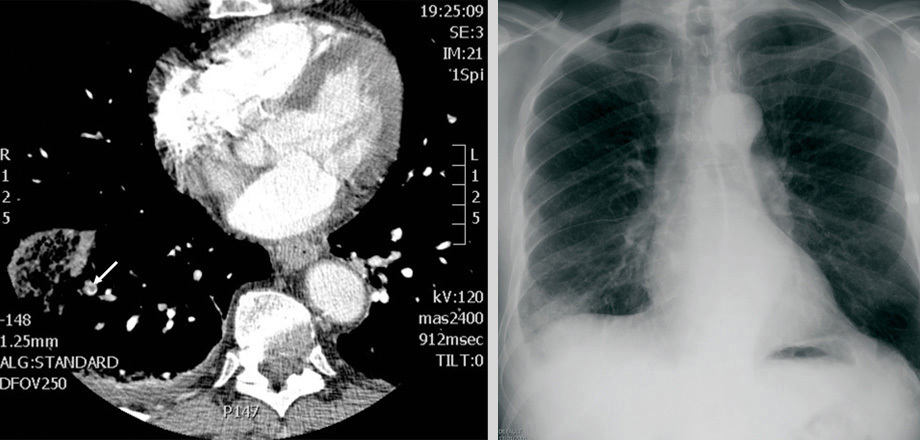

Aspects radiologiques de l'embolie pulmonaire : Infarctus pulmonaire.